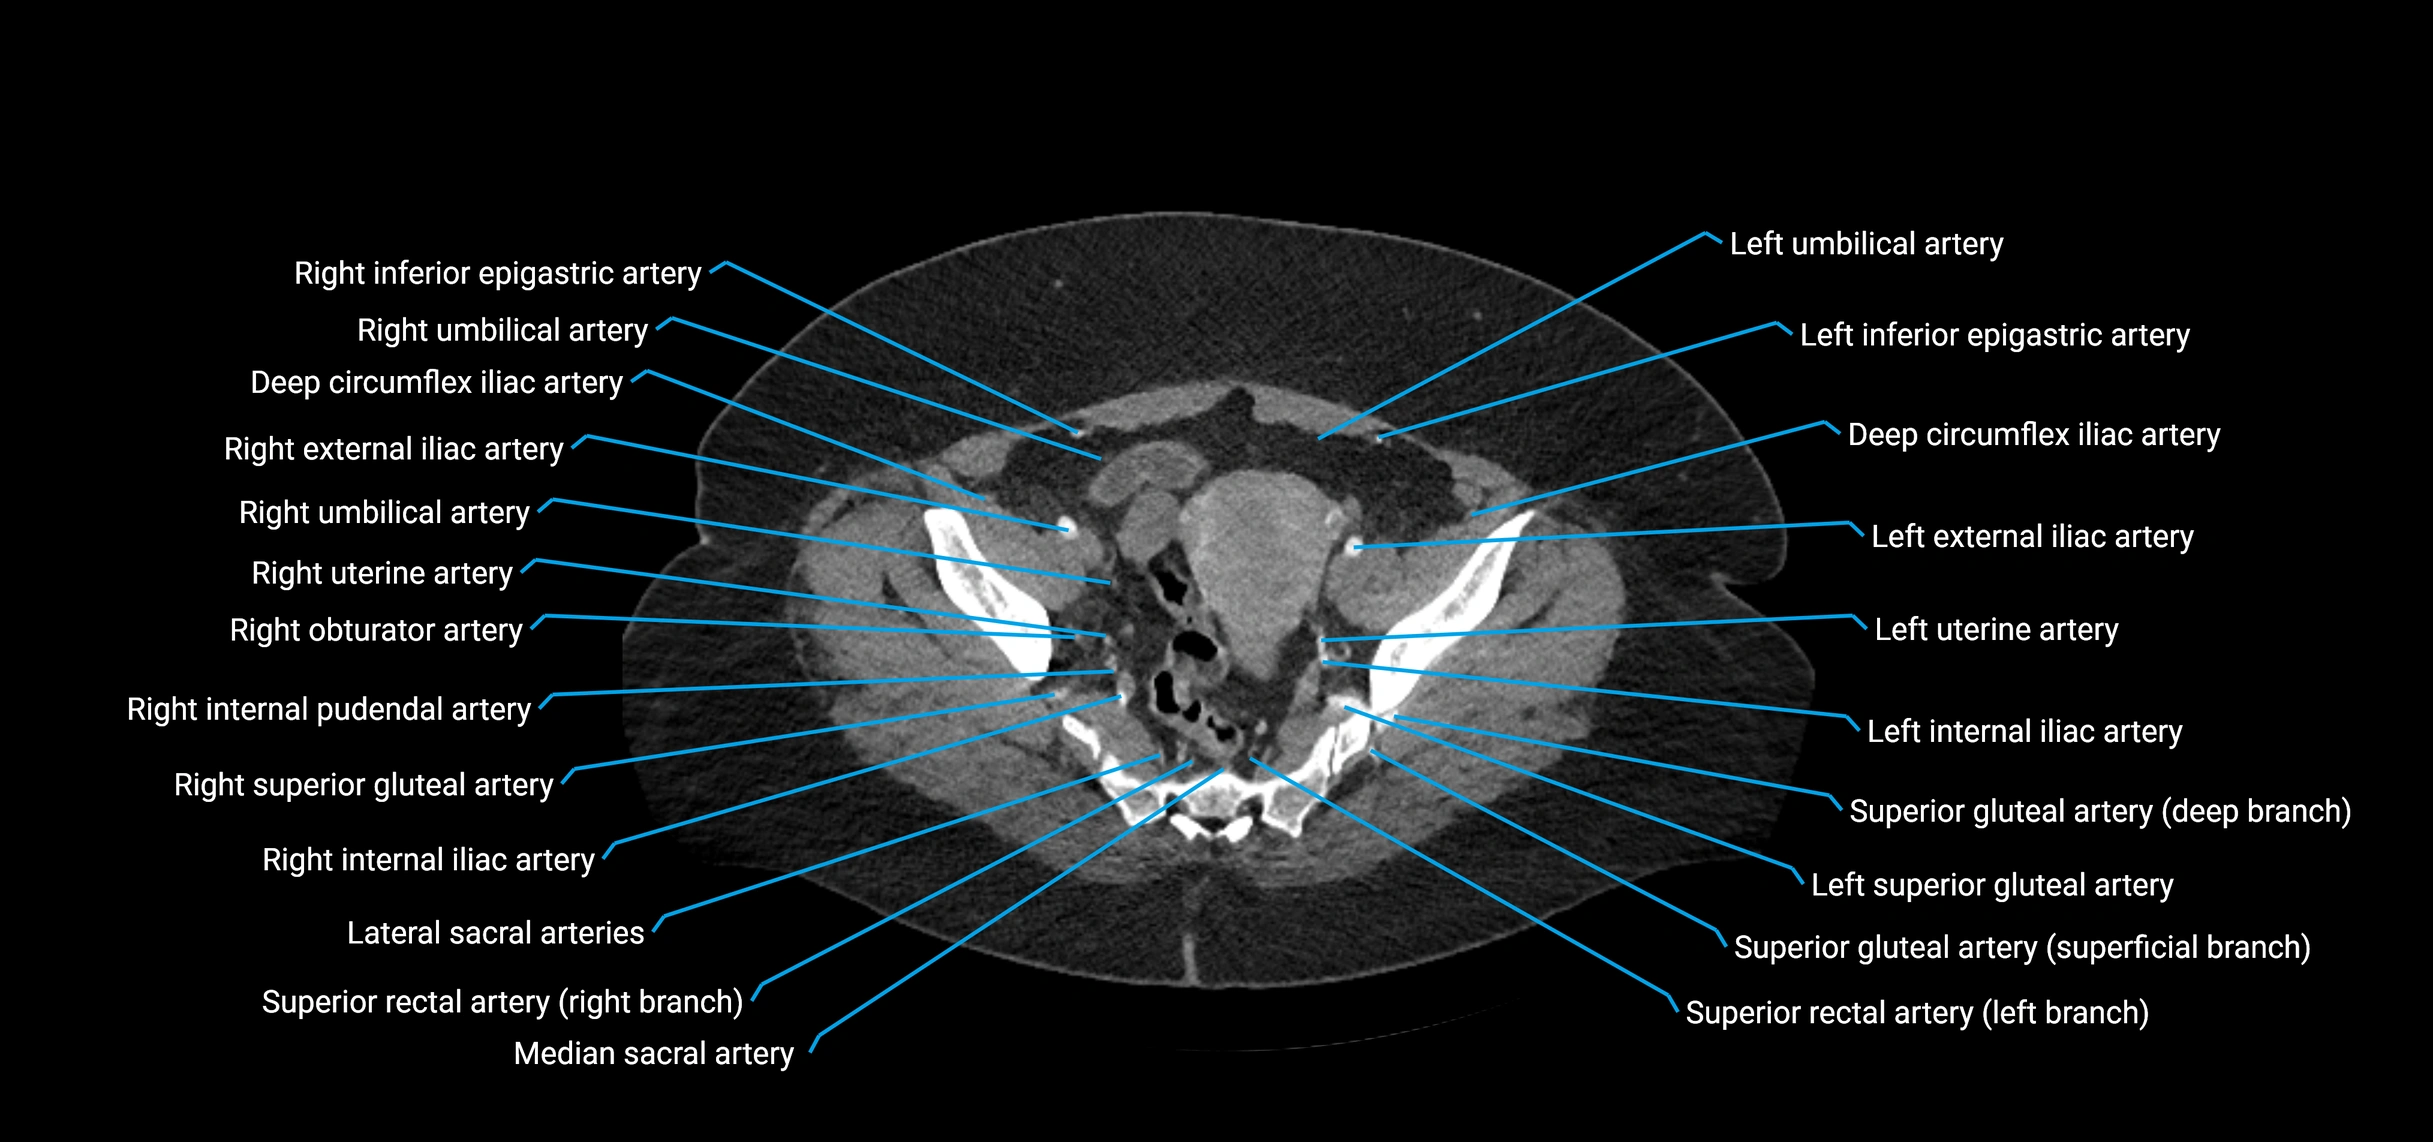

CT images

image